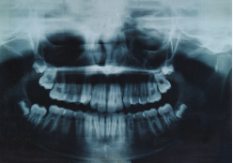

Radiologie dentaire